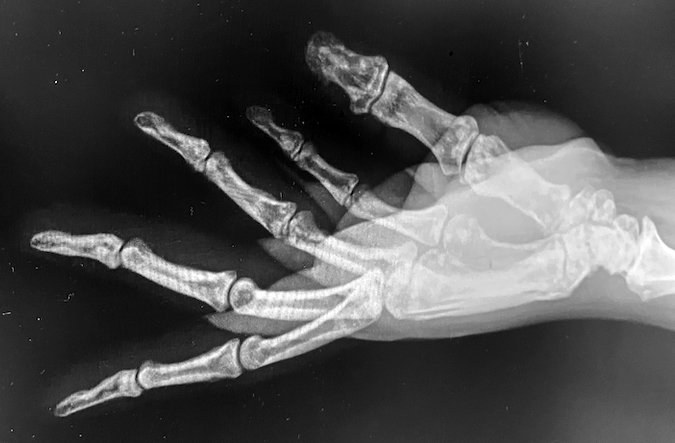

OSTEOPOIKILOSIS

• Osteopoikilosis right hand AP X-ray with a Boxer's fracture (arrow)

Osteopoikilosis right hand AP X-ray with a Boxer's fracture (arrow)